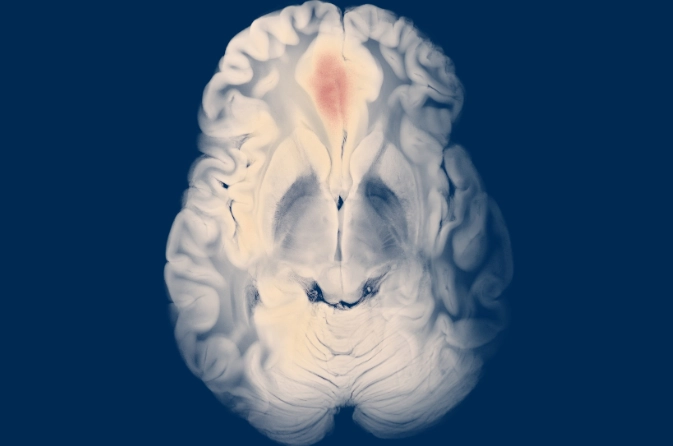

Epidural Hematoma Surgery is performed to remove blood pooled between the skull and the outer layer of the brain, known as the dura mater. This condition usually occurs due to trauma, accidents, or skull fractures and leads to rapid pressure buildup. The surgery prevents brain damage, restores blood flow, and stabilizes the patient. Early intervention is critical for successful recovery.